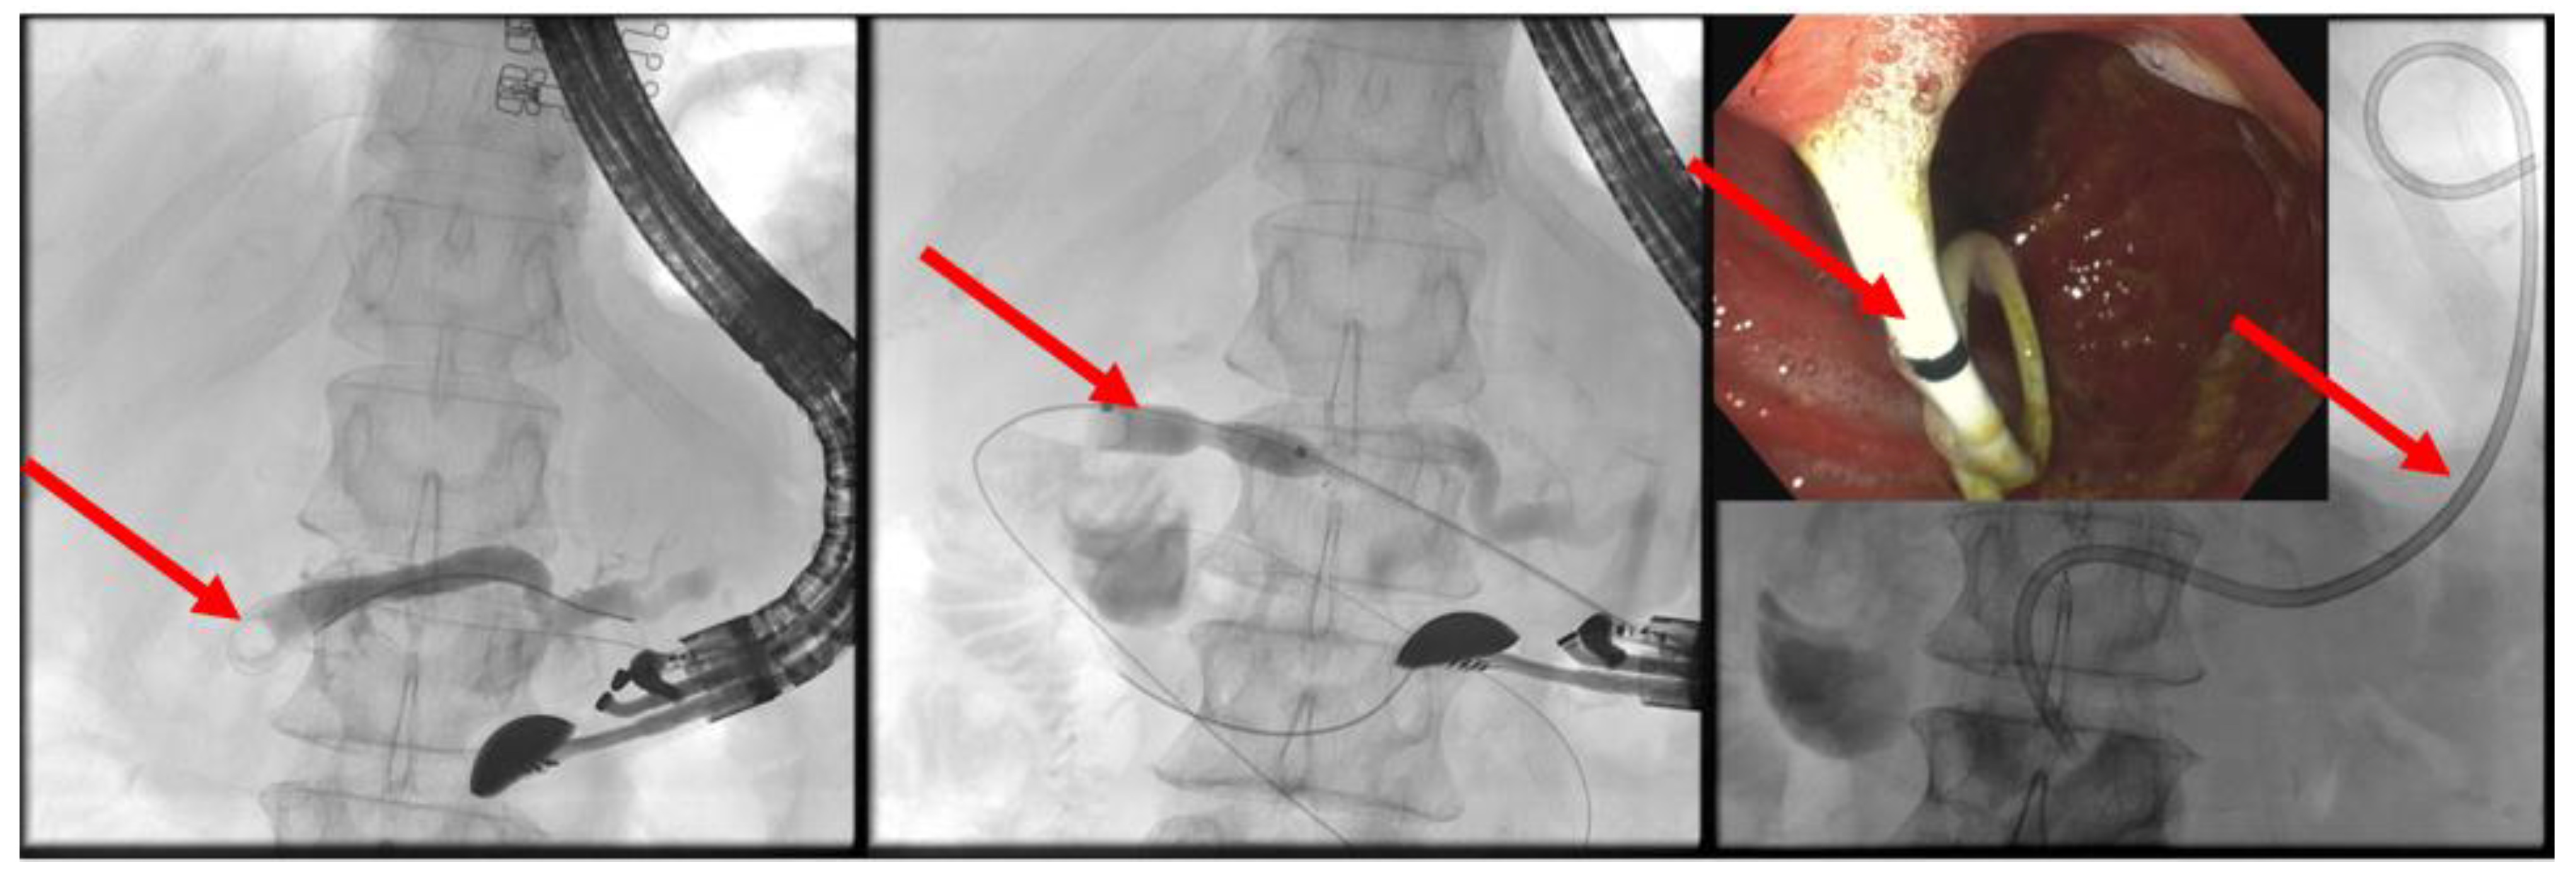

(A) EUS-ERP rendezvous technique: If the wire can be passed through the papilla and the papilla is accessible with the endoscope, a duodenoscope is employed. The guidewire is then grasped with forceps and pulled out, enabling subsequent conventional ERP with endoscopic papillary balloon dilation (EPBD) and stent placement (Figure 3 and Figure 4).

Figure 3. EUS puncture with a 19-G needle tangentially toward the papilla; the wire is passed out of the papilla via a ring knife, followed by device change of the duodenoscope.

Figure 4. After the device change, the wire is grasped with forceps and passed out, followed by a conventional ERP with stent placement (red arrow).